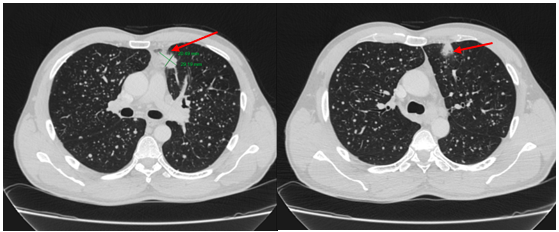

-         MRI sọ não:

Hình 4. Trên phim chụp MRI sọ não: Rải rác trong nhu mô trên và dưới lều có các nốt ngấm thuốc, lớn nhất vị trí cạnh não thất bên bên phải đường kính ~11mm – Theo dõi tổn thương thứ phát

Cộng hưởng từ sọ não:

Sau 6 tháng điều trị: Nhu mô não vùng trên và dưới lều tiểu não: hình dạng và cấu trúc bình thường, tín hiệu đồng nhất, ranh giới chất trắng và chất xám rõ. Không thấy tổn thương khu trú hoặc lan tỏa.